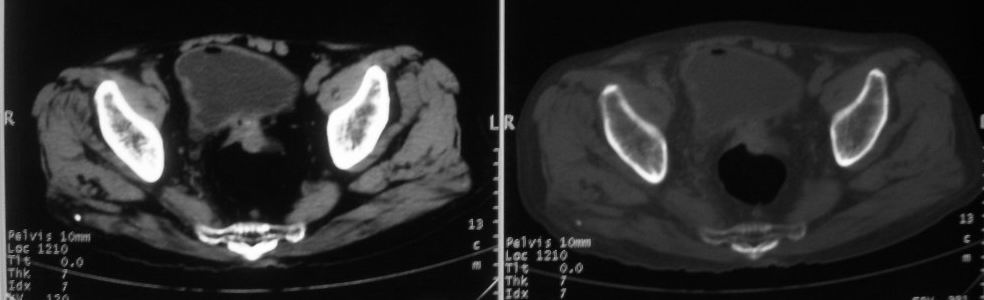

以下是引用深泽交通医院在2008-10-3 15:33:00的发言:[br]前列腺实性增大伴分叶状,与包膜间隙境界不清;椎体松质区间结节样密度影,考虑:前列腺癌,并椎体成骨性转移